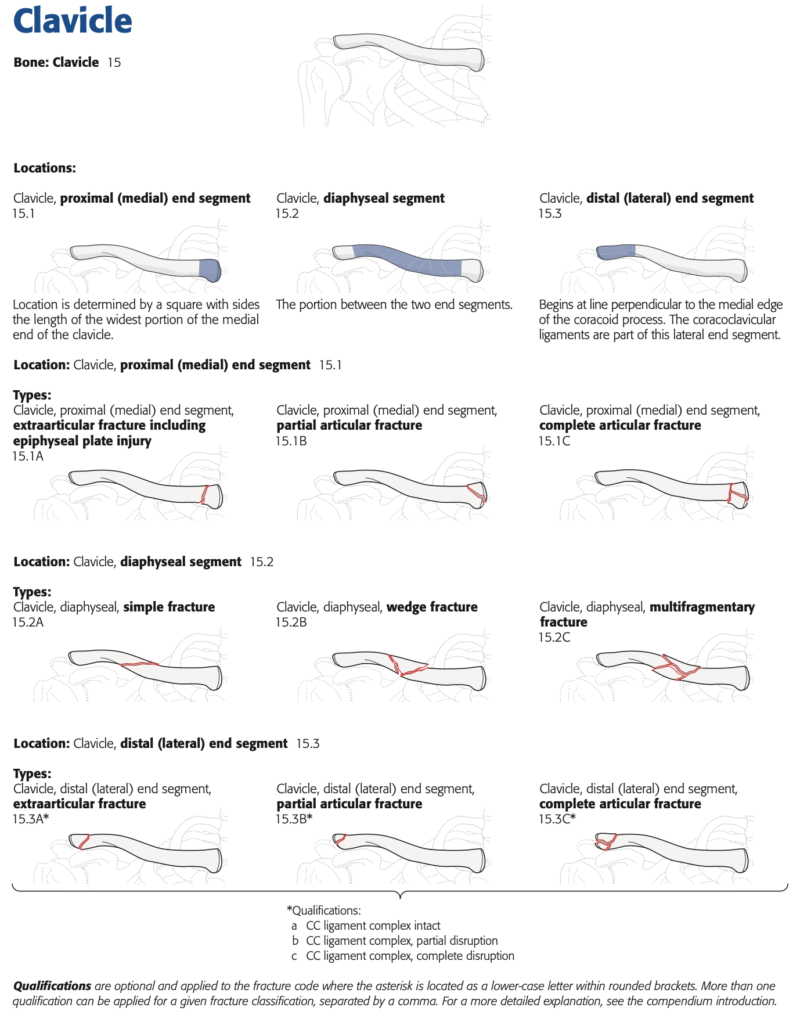

整形外科クリニックの後輩医師から鎖骨骨折の高齢の患者さんが手術を希望されて, 紹介されて受診されました. 飲酒後に転倒されて, 同じ側のあばら骨(肋骨)も3本骨折していました. 鎖骨の骨折は, 中央部で骨のかけら(骨片こっぺん)を生じた骨折で, AO/OTA分類では15.2Bでした(上図参照).